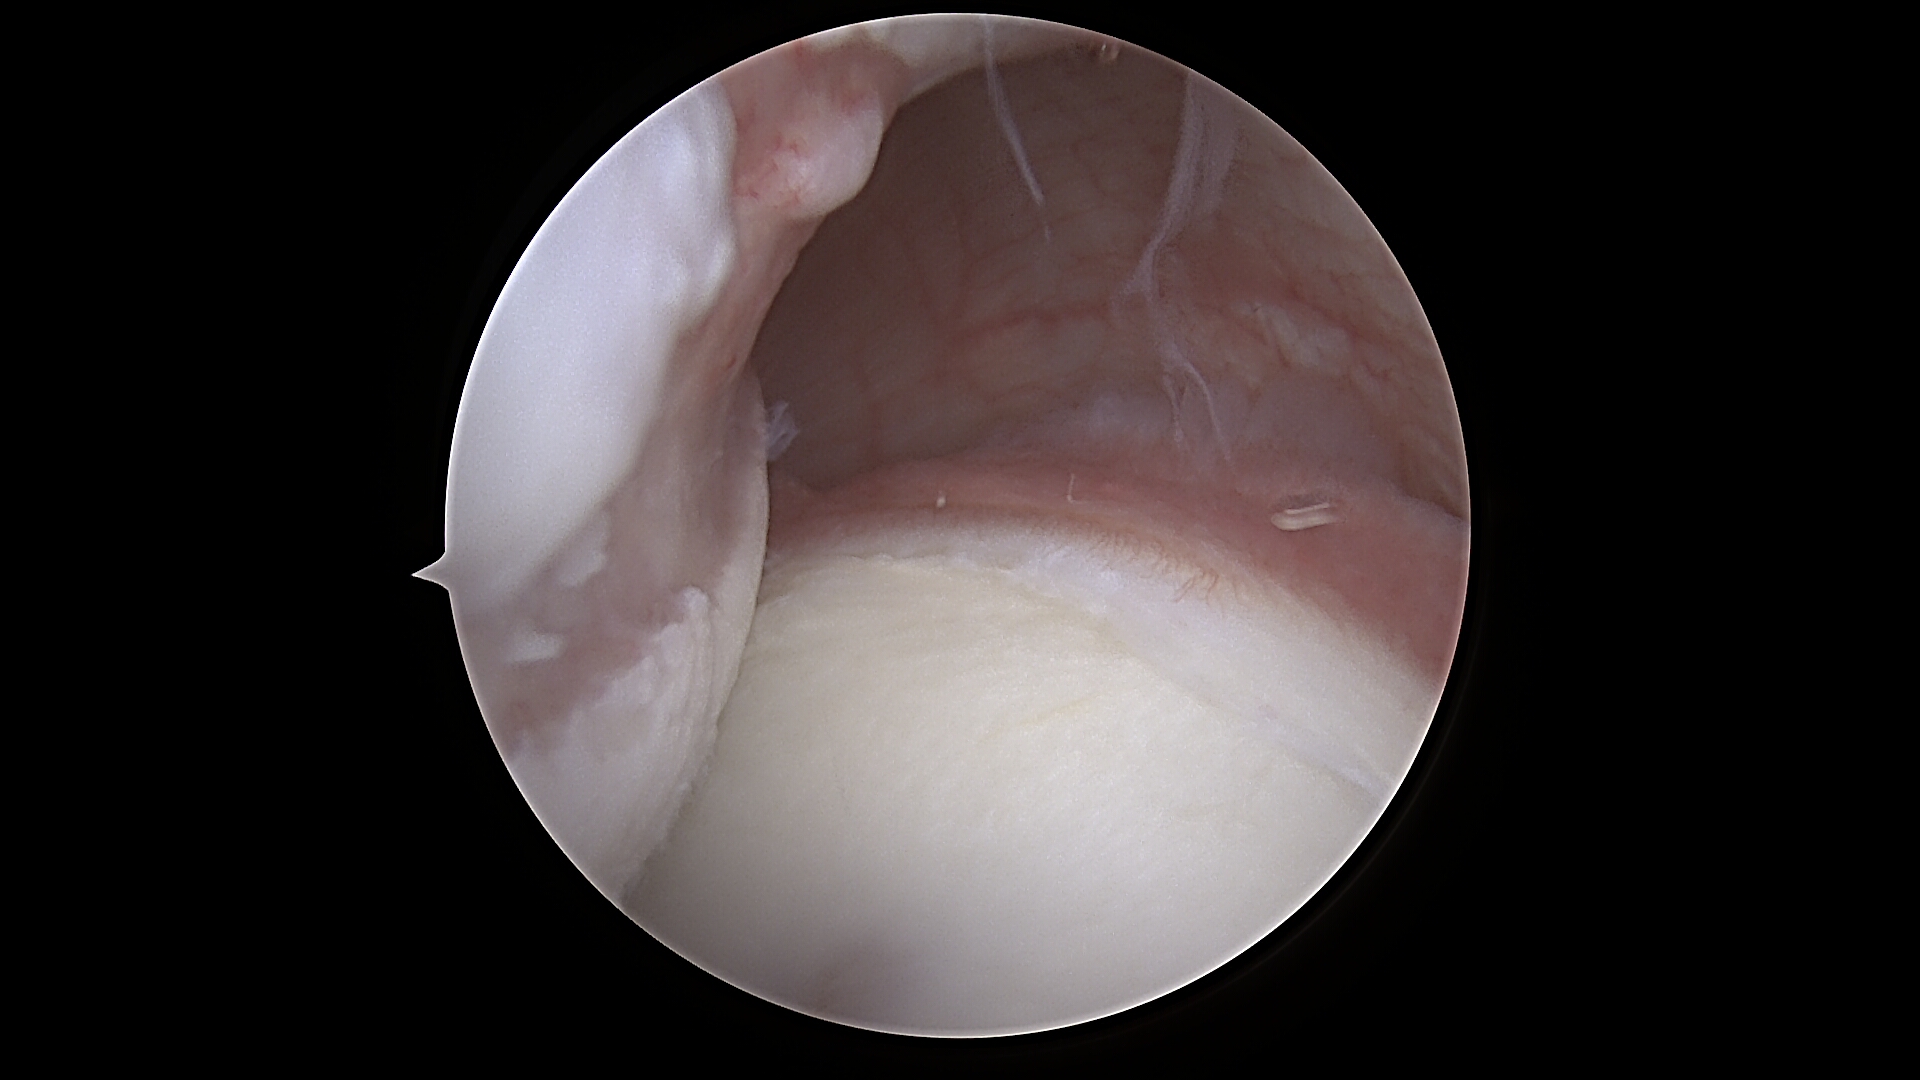

Il termine “Remplissage” deriva dal francese e significa letteralmente “riempimento”. Questa tecnica è stata descritta per la prima volta nel 2007 da Wolf e colleghi come soluzione per ridurre il rischio di recidiva nei pazienti con lesione di Hill-Sachs (HS) “engaging”. La lesione di Hill-Sachs consiste in una depressione postero-laterale della testa omerale che si genera durante la lussazione anteriore della spalla (fig.1). Quando questa deformità “impegna” il bordo glenoideo anteriore durante i movimenti di traslazione, aumenta il rischio di nuove lussazioni.

Fig.1: visione intraoperatoria dal portale antero-superiore di lesione Hill-Sachs